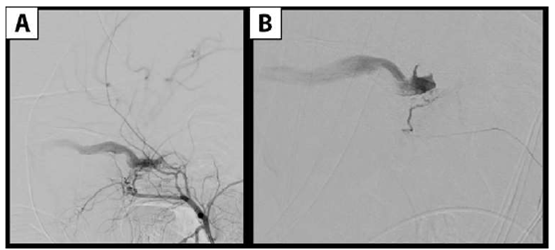

La arteriografía evidencia fístula carótido-cavernosa indirecta izquierda tipo D de la clasificación de Barrow. Presenta aferencias provenientes de la arteria carótida interna izquierda a través de un fino ramo corto carótido hipofisario, y de carótida externa izquierda a través de finos ramos de la arteria maxilar interna. El drenaje se produce hacia una vena oftálmica superior dilatada con flujo lento y hacia los senos petrosos (Figura 2yFigura 3).

Figura 3:Angiografía digital que muestra FCC indirecta izquierda tipo D de la clasificación de Barrow, alimentada por la arteria carótida externa izquierda a través de finos ramos de la arteria maxilar interna. Seevidencia el drenaje hacia el seno cavernoso y de ahí a una dilatada vena oftálmica superior.A) Inyección por carótida externa izquierda, proyección lateral. B) Inyección supraselectiva con microcateter desde un fino ramo de maxilar interna.